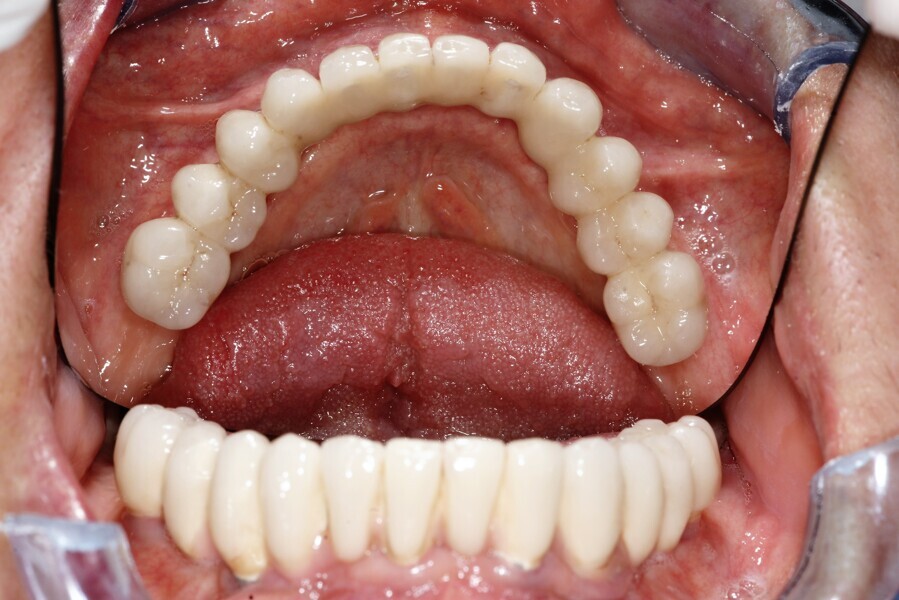

Natychmiastowa implantacja i zaopatrzenie protetyczne pacjentów z zaawansowaną chorobą przyzębia